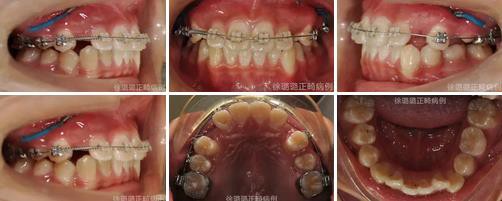

360截圖20170120124750762.jpg

導(dǎo)萌術(shù)中口內(nèi)像

CT 片結(jié)果顯示,上頜雙側(cè)側(cè)切牙與尖牙位置較近,因此早期沒有粘結(jié)雙側(cè)側(cè)切牙托槽,以防止正畸加力對(duì)牙齒造成根尖吸收。